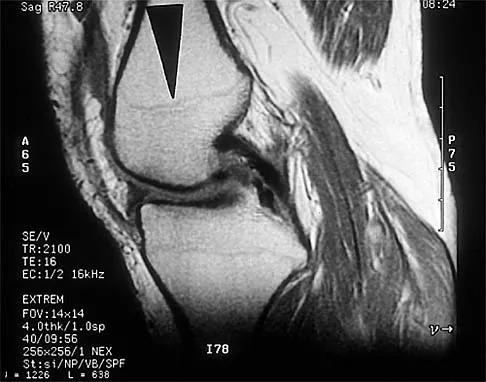

A 28-year-old professional dancer reports a 3-month history of progressive pain in the posterior aspect of the left ankle. Her symptoms are worse when she assumes the en pointe position. Examination reveals tenderness to palpation at the posterolateral aspect of the ankle posterior to the peroneal tendons which is made worse with passive plantar flexion. There is no nodularity, fluctuance, or tenderness of the Achilles tendon. The neurovascular examination is unremarkable. A lateral radiograph and MRI scan are shown in Figures 16a and 16b, respectively. Management should consist of

The imaging studies reveal findings typical of the os trigonum syndrome. This condition results from inflammation between the os trigonum and the adjacent talus. The symptoms of posterior ankle pain are exacerbated by plantar flexion, which stresses the fibrous union between these two bones. Definitive management of the high-level athlete involves excision of the os trigonum from a medial approach, although arthroscopic excision has also been described. The os trigonum is not an intra-articular structure; therefore, ankle arthroscopy is neither diagnostic nor therapeutic. Abramowitz Y, Wollstein R, Barzilay Y, et al: Outcome of resection of a symptomatic os trigonum. J Bone Joint Surg Am 2003;85:1051-1057. Mouhsine E, Crevoisier X, Leyvraz P, et al: Post-traumatic overload or acute syndrome of the os trigonum: A possible cause of posterior ankle impingement. Knee Surg Sports Traumatol Arthrosc 2004;12:250-253.